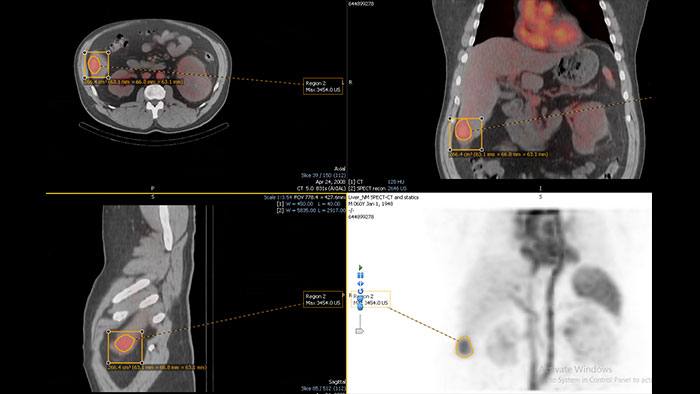

Mirada NM Viewer: Mirada XD 3.6

Mirada NM Viewer: Mirada XD 3.6*

Enhanced user experience for NM reading with a leading NM viewing solution

A comprehensive NM solution, designed to enhance productivity of PET/CT and NM reading. It offers a solution for handling multiple studies requiring rigorous quantification of MV data**.

• Quick and configurable protocols for efficient reading.

• Lesion tracking and treatment response.

• Exportable tables and graphs.

• PET\CT and PET\CT\MR registration.